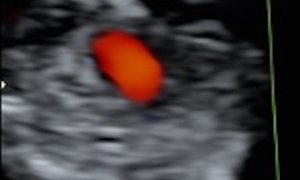

Caso del Mese di Dicembre 2021

Cari soci, finalmente la soluzione del caso del mese di Dicembre! Scarica il File L'attesa è finita: Al seguente link la...